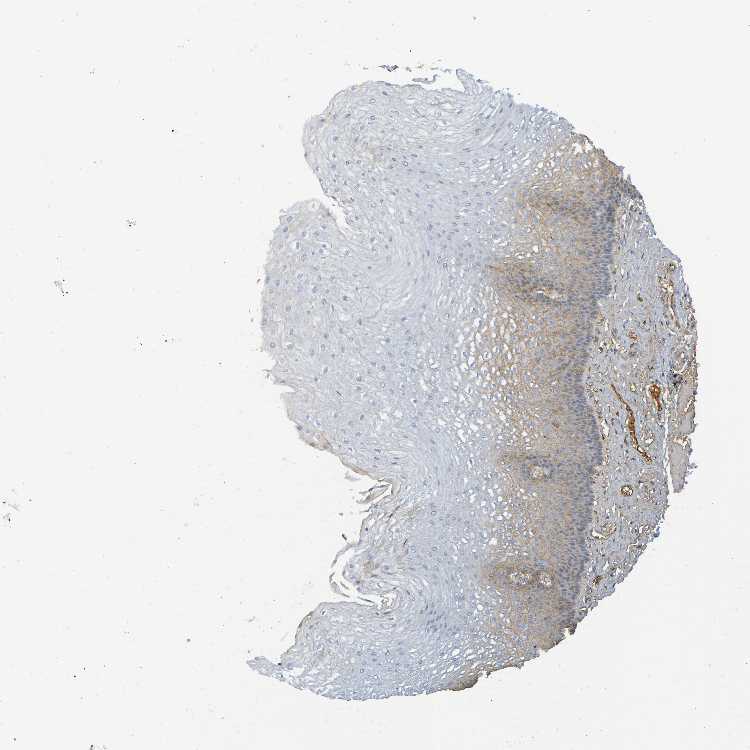

ESOPHAGUS - Antibody stainingi

Antibody staining in the annotated cell types in the current human tissue is reported as not detected, low, medium, or high, based on conventional immunohistochemistry profiling in selected tissues. This score is based on the combination of the staining intensity and fraction of stained cells.

Each image is clickable and will lead to virtual microscopy that enables deeper exploration of all samples and also displays staining intensity scores, fraction scores and subcellular localization as well as patient and tissue information for each sample.

Antibody HPA002350Antibody CAB009823

Squamous epithelial cells Not detectedLow